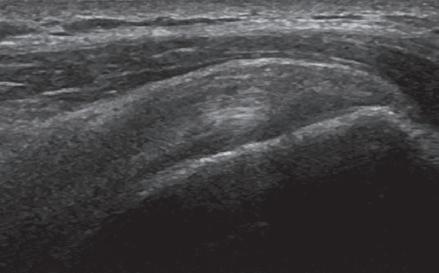

FIGURE 1.11 Anisotropy. Ultrasound images of distal supraspinatus tendon in long axis (S) shows an area of hypoechoic anisotropy (curved arrow) (A), where the tendon fibers become oblique to the sound beam, which is eliminated (B) when the transducer is repositioned so that the tendon fibers are perpendicular to the sound beam. H, Humerus.